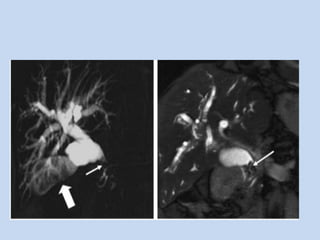

• In Choledocholithiasis :

- On MRCP stones appear as signal void in the

- number, size & location are determined.

- stones as small as 2mm can be identified with current

APPLICATIONS • In Choledocholithiasis: - USG & CT are often used in the initial evaluation in suspected choledocholithiasis. - On MRCP stones appear as signal void in the background of high signal intensity bile. - number, size & location are determined. - stones as small as 2mm can be identified with current techniques.